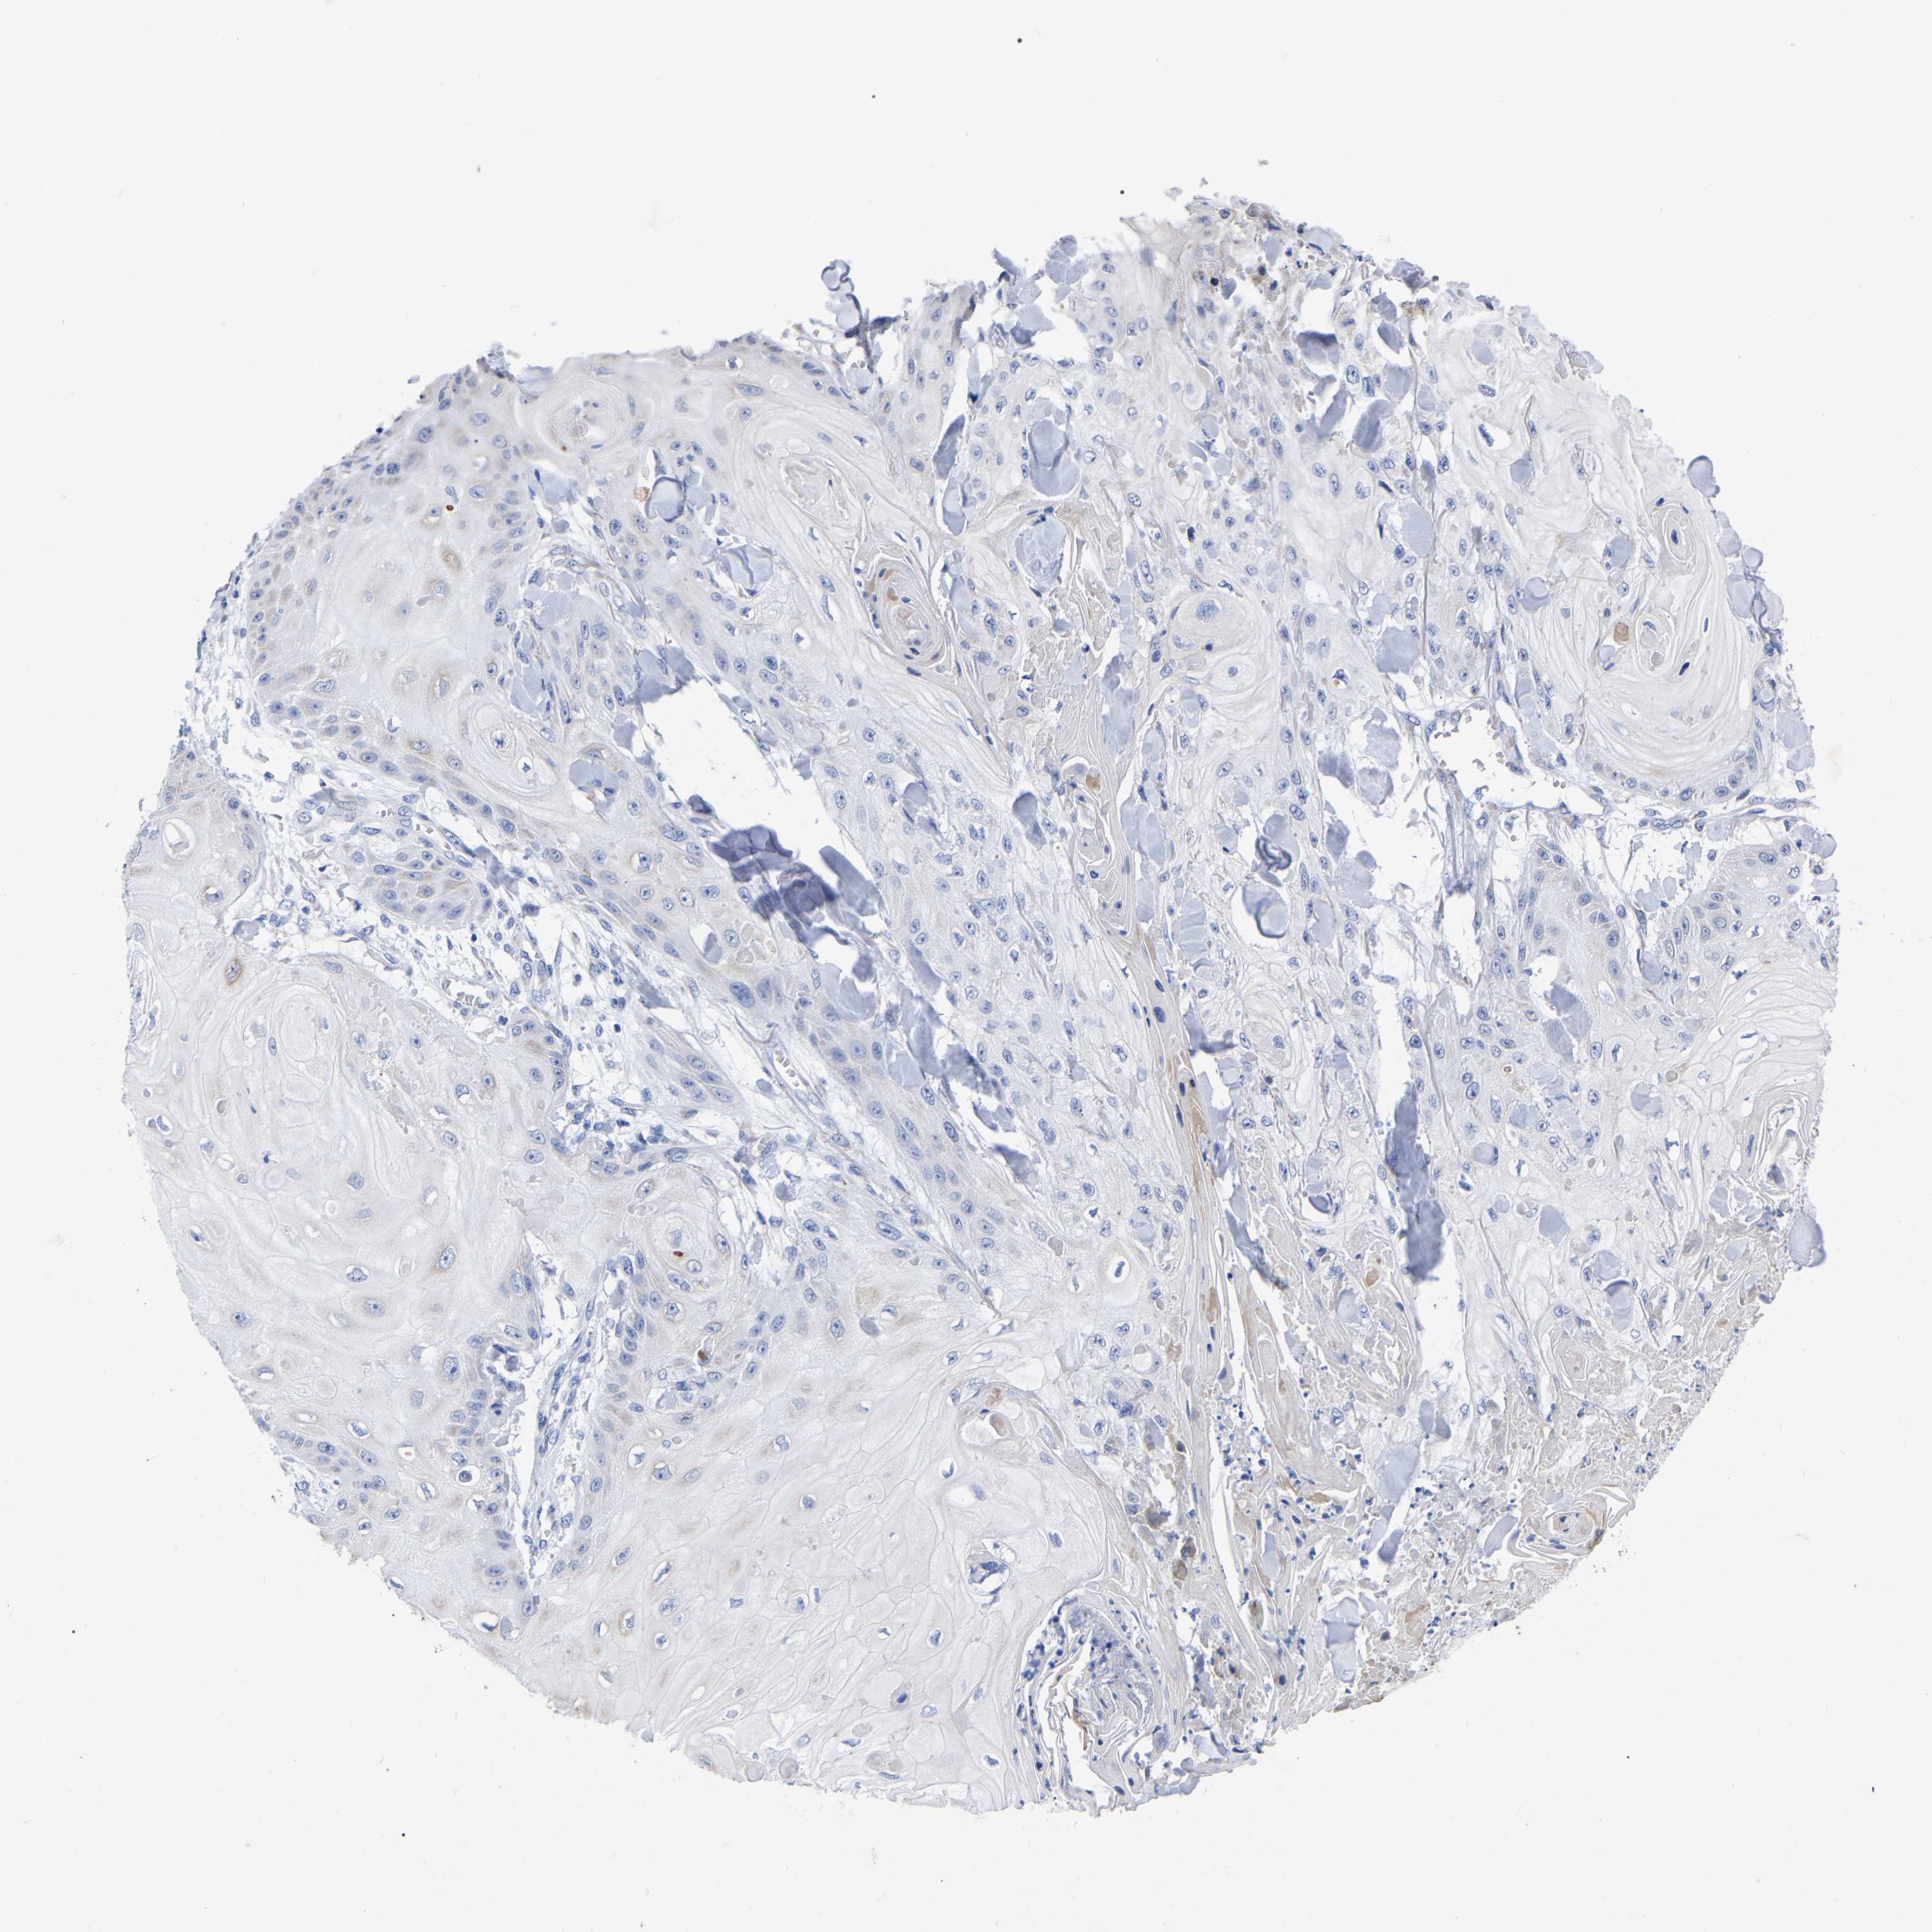

SKIN CANCER - Protein expressioni

A mouse-over function shows sample information and annotation data. Click on an image to view it in a full screen mode. Samples can be filtered based on level of antibody staining by selecting one or several of the following categories: high, medium, low and not detected. The assay and annotation is described here.

Each image is clickable and will lead to virtual microscopy that enables deeper exploration of all samples and also displays staining intensity scores, fraction scores and subcellular localization as well as patient and tissue information for each sample.

Antibody HPA018468

Basal cell carcinoma